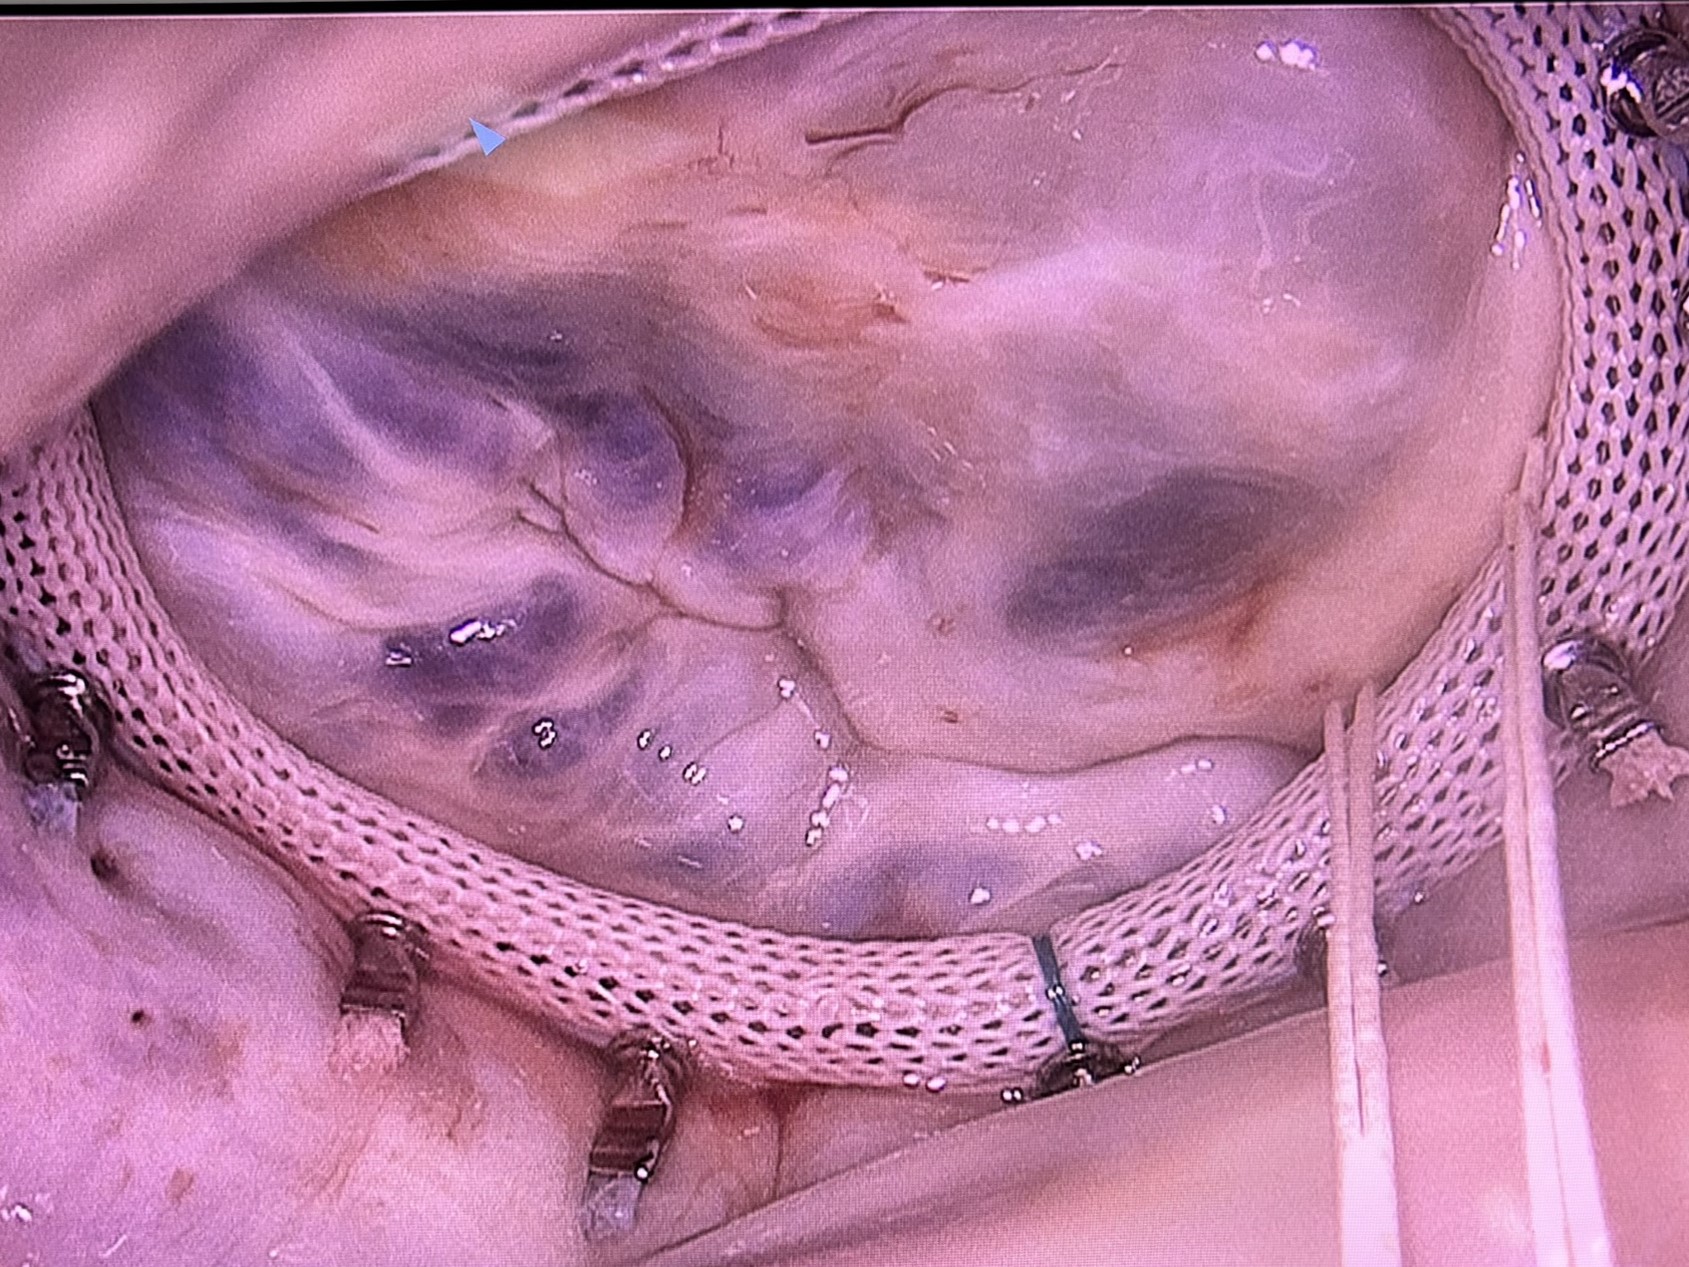

În functie de mecanismul regurgitarii mitrale, se aplica diferite metode de plastie ale acesteia:

Procedura comuna în reparatia valvei mitrale o reprezinta anuloplastia cu inel. Anuloplastia se realizează prin montarea unui inel sintetic cu rolul de a reda si a stabiliza forma corectă a inelului valvei mitrale a pacientului.

La bărbați, incizia de 4-6 cm se efectuează prin toracotomie antero-laterală dreapta prin spațiul III sau IV intercostal, adică o incizie mică printre coaste, iar la femei in functie de aspectul glandei mamare drepte.